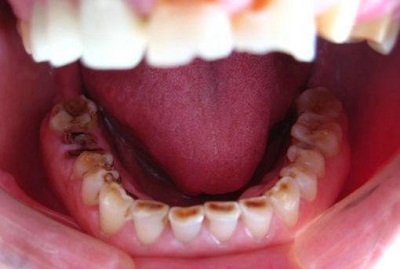

5.清洁不易

长期食物堆积会造成牙齿的牙周破坏及蛀牙。此外若牙齿有向缺牙区移动的状况则会和邻牙产生过大的缝隙,咀嚼食物时也会容易塞在牙缝。